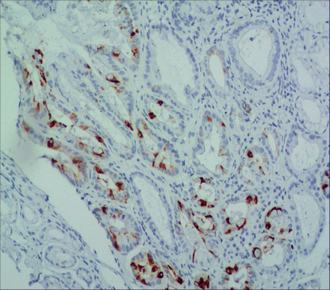

| 适用组织: | 石蜡切片 |

| 阳性部位: | 细胞质 |

| 阳性对照: | 结肠癌 |

| 特异性 : | 此抗体与人的粘蛋白2反应,其它种属未检测。 |

| 推荐效价: | •原液使用前应以适当比例稀释 推荐稀释度为1:50~1:100 •工作液不必稀释,直接滴加使用 |